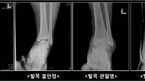

30대 박모씨는 1년 전 농구경기를 하던 중 발목을 삐어 동네 병원을 찾았다. 진료 및 X-ray 촬영을 한 결과 큰 이상이 없다는 말을 듣고, 특별한 치료 없이 지나쳤다. 이후 다시 농구를 하다 발목을 삐게 되었는데, 이전과는 다르게 수주가 지나도 발목 통증이 나아지지 않았다. 일반 X-ray 촬영상 특이 소견이 없어 MRI촬영을 하게 되었고, 그...